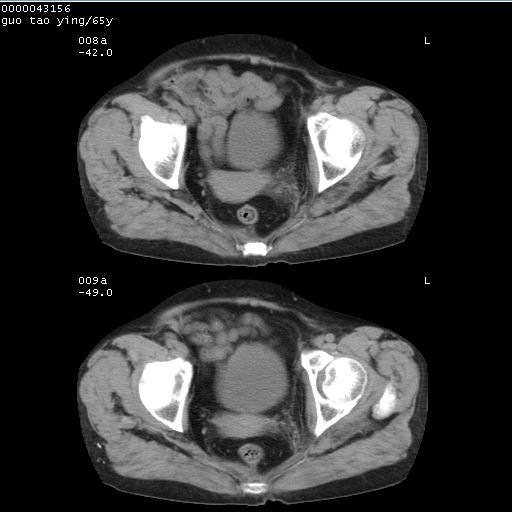

以下是引用黑白光影在2008-1-30 13:22:00的发言:[br]支持左耻骨骨折。[br]未见骶骨骨质明确破坏改变。[br]经楼主提示(勿局限于外伤)。考虑为右侧腹股沟直疝。[br][br][br][br]